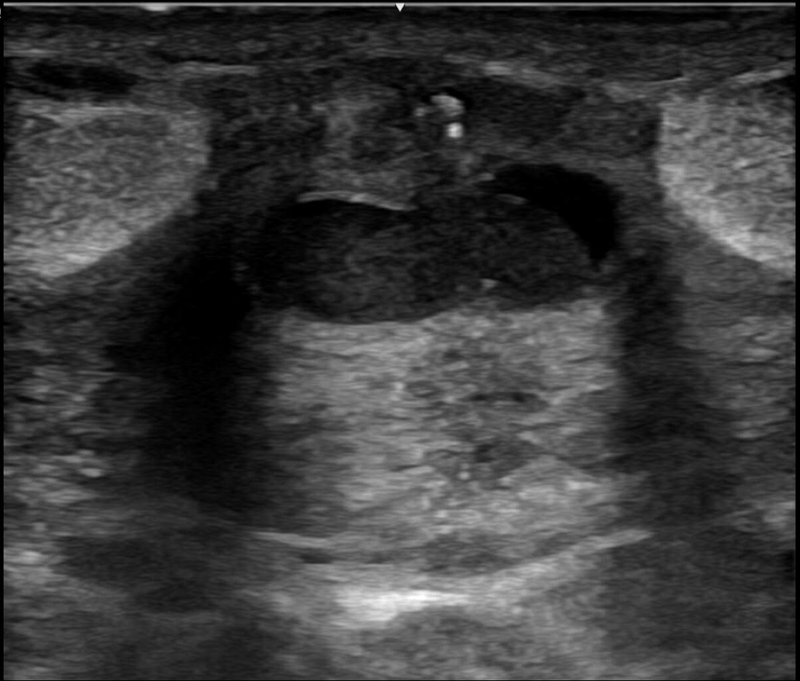

Adolescente de 13 años que acude a Urgencias por dolor en la mama derecha de una semana de evolución. Afebril. Niega telorrea, traumatismo previo o menstruación actual. No presenta antecedentes personales de interés, pero sí antecedentes familiares de cáncer de mama en madre y abuela materna.